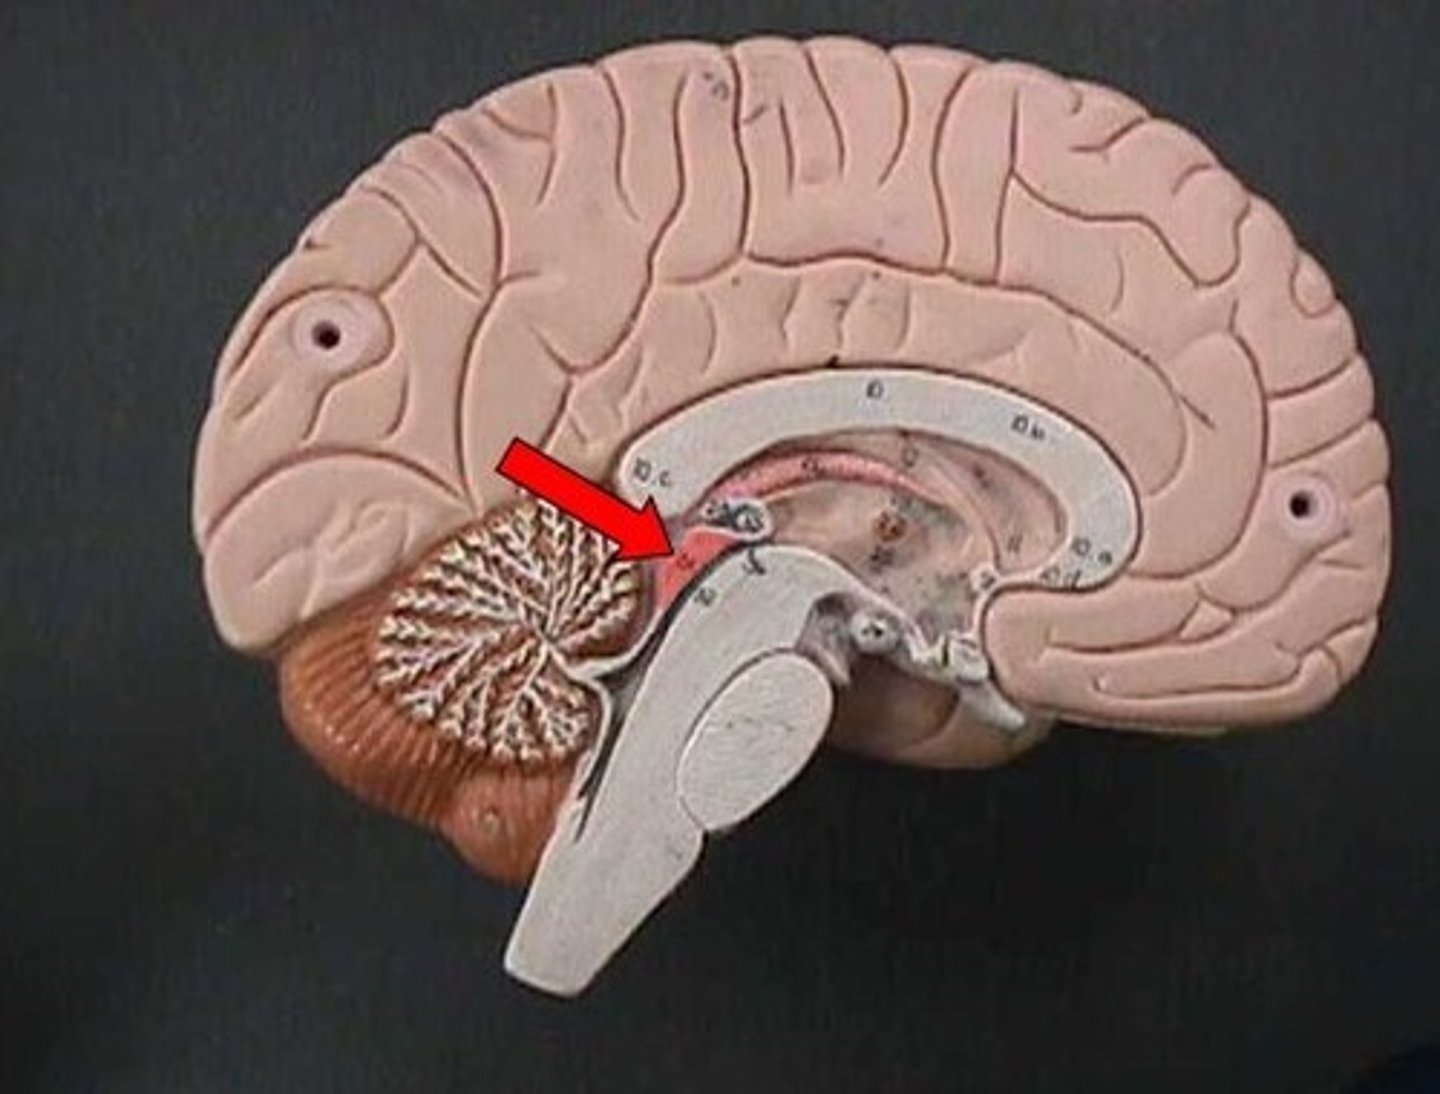

cerebellum

balance, equilibrium, gross motor movement

arbor vitae

"tree of life," white matter of cerebellum

cerebrum

corpus callosum

the large band of neural fibers connecting the two brain hemispheres and carrying messages between them

septum pellucidum

membrane that separates lateral ventricles

basal nuclei

internal masses of gray matter, smooth out motor movement

fornix

band under septum pellucidum

diencephalon

thalamus and hypothalamus

thalamus

relay station for all somatosensory information

intermediate mass

connection between the two thalami across the third ventricle, dumbbell shape

hypothalamus

brain region (many nuclei) in charge of maintaining homeostasis

pituitary gland

produces hormones

mammillary bodies

olfactory relay stations

epithalamus

region above midbrain that contains pineal gland

pineal gland

regulates sleep-wake cycles, secretes melatonin

medulla oblongata

basic life support, heart beating, etc.

decussation of pyramids

where the cleavage furrow becomes almost flat - the reason for contralateral control

pons

control of breathing

midbrain

immediate reflexes

cerebral peduncles

connect lower and upper brain, cerebrum to brainstem

corpora quadrigemina

located in the midbrain; contains reflex centers for vision and auditory reflexes.

superior colliculi

part of corpora quadrigemina, visual reflexes

inferior colliculi

part of corpora quadrigemina, auditory reflexes